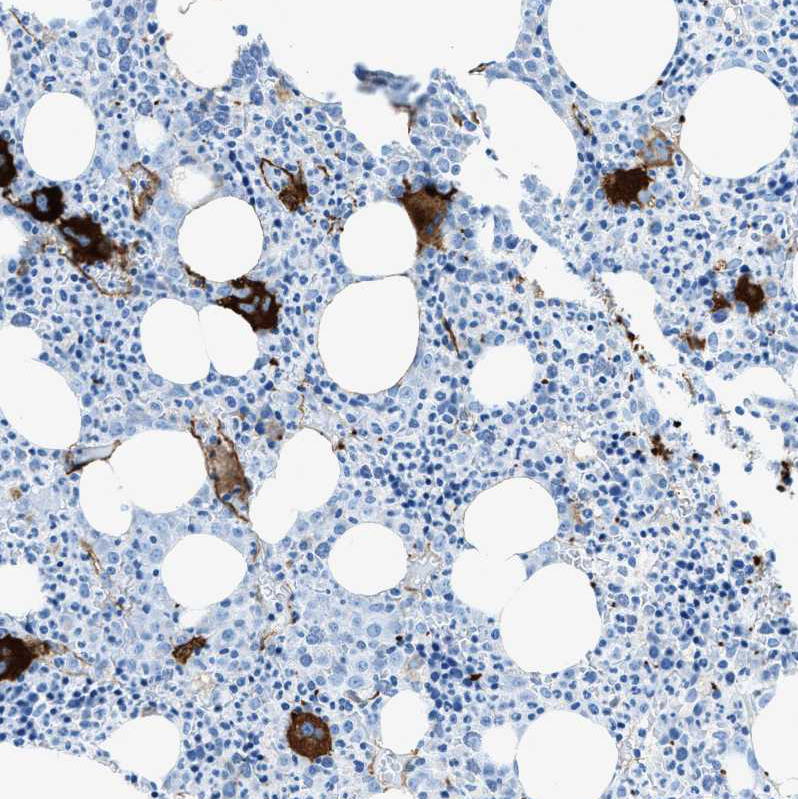

Immunohistochemical staining of human bone marrow shows strong cytoplasmic positivity in megakaryocytes.